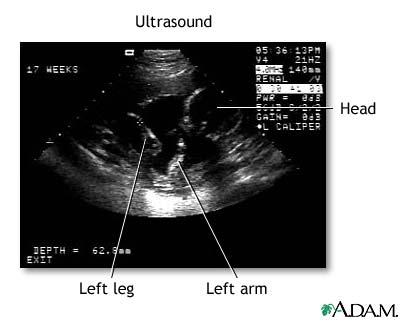

Ultrasound - series: Procedure, part 3

• Don't get your hopes up too much about this first, fleeting look at your baby. The black-and-white image you see on the computer screen is grainy, shadowy, and may look more like a test pattern than a baby-to-be. Your sonographer will walk you through what you're seeing by pointing out the fetus' developing heart, limbs, and head.